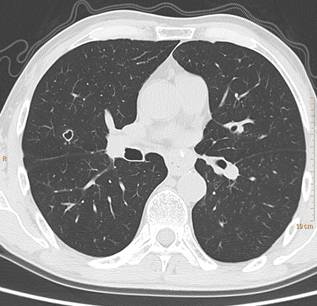

CT影像常多发,多为圆形,壁薄,光滑均匀,也可以表现为厚薄不一,肺门侧的壁较厚,外侧的壁薄,也可出现厚壁空洞,空洞壁常有明显强化。空洞性病变倾向于分布在胸膜下或叶间裂下,越靠近胸膜,空洞越小,直径较大的空洞多分布在肺的中带。厚壁空洞病变可随着病灶增大而出现分叶、毛刺及壁结节等恶性空洞的特点。 医学百科网 | YxBaike.Com

空洞性肺转移瘤变化快,短期内可见肿瘤增大、增多,有时可在治疗后自行消失。有学者认为空洞壁厚1-2mm及以下者不太符合缺血坏死所形成空洞的形态,因而称空泡更合适。空泡样转移瘤的瘤壁菲薄光滑,质均匀,可与肺纹理相连。